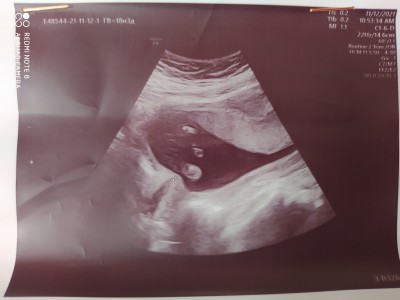

Canım bir foto daha ekledim peki orda pipi gozukuyomu

Onları anlayamdım, ama doktor önden gormuştur erkekler hemen belli ediyor

Kızlar onceki resimleri de atdım bakarmisiiniz